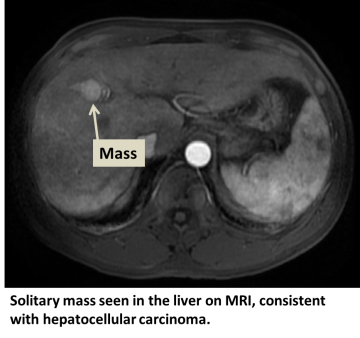

Hepatocellular carcinoma (HCC) is the most common type of primary liver cancer. Primary liver cancer refers to cancer that originates in the liver rather than cancers from other organs that metastasize to the liver (see metastatic liver cancer). HCC can start as a single tumor or as several tumor nodules across the liver.

Diagnosis and Screening

In addition to a physical examination, laboratory tests and imaging studies may be needed. These tests may also be necessary at regular intervals to detect early cancer if certain risk factors are present. Our physicians may enroll you into such a screening or surveillance program. The tests may include:

- Ultrasound

- CT scan

- MRI